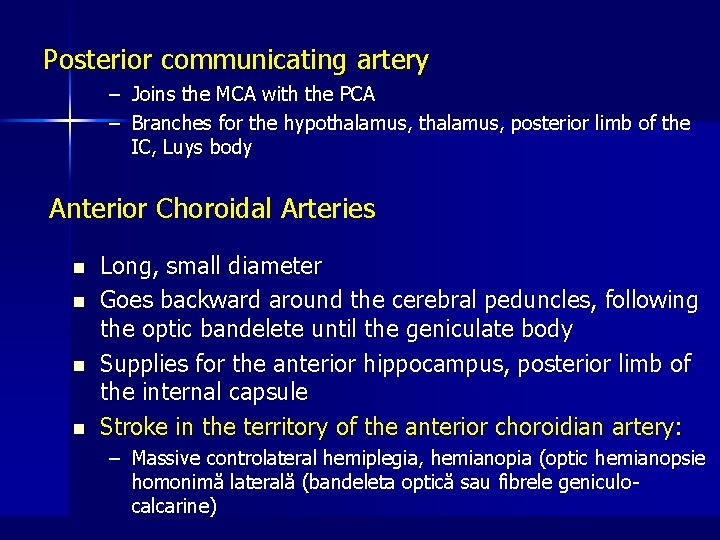

Posterior communicating artery – Joins the MCA with the PCA – Branches for the hypothalamus, posterior limb of the IC, Luys body Anterior Choroidal Arteries n n Long, small diameter Goes backward around the cerebral peduncles, following the optic bandelete until the geniculate body Supplies for the anterior hippocampus, posterior limb of the internal capsule Stroke in the territory of the anterior choroidian artery: – Massive controlateral hemiplegia, hemianopia (optic hemianopsie homonimă laterală (bandeleta optică sau fibrele geniculocalcarine)